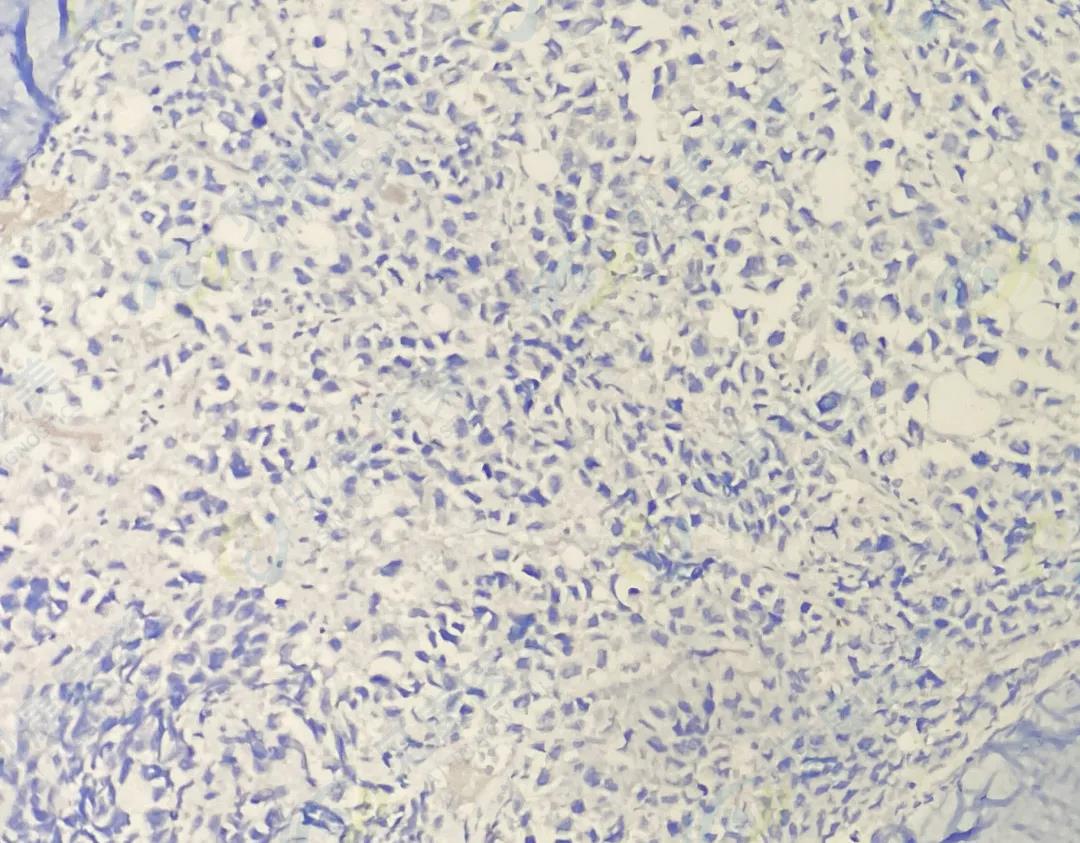

CD138

CD38

κ

λ